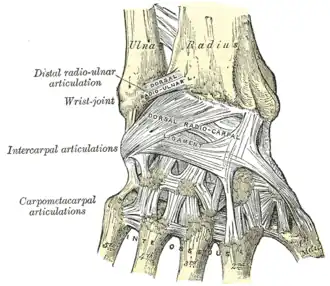

Ligamentos do pulso.

As articulações carpometacarpais(CMC) são cinco articulações no punho que se articulam com a porção distal dos ossos carpais e basais de cinco ossos metacarpais.